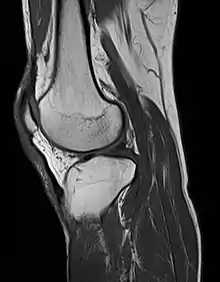

Magnetic resonance imaging

MRI uses strong magnetic fields to align atomic nuclei (usually hydrogen protons) within body tissues, then uses a radio signal to disturb the axis of rotation of these nuclei and observes the radio frequency signal generated as the nuclei return to their baseline states.[10] The radio signals are collected by small antennae, called coils, placed near the area of interest. An advantage of MRI is its ability to produce images in axial, coronal, sagittal and multiple oblique planes with equal ease. MRI scans give the best soft tissue contrast of all the imaging modalities. With advances in scanning speed and spatial resolution, and improvements in computer 3D algorithms and hardware, MRI has become an important tool in musculoskeletal radiology and neuroradiology.

One disadvantage is the patient has to hold still for long periods of time in a noisy, cramped space while the imaging is performed. Claustrophobia (fear of closed spaces) severe enough to terminate the MRI exam is reported in up to 5% of patients. Recent improvements in magnet design including stronger magnetic fields (3 teslas), shortening exam times, wider, shorter magnet bores and more open magnet designs, have brought some relief for claustrophobic patients. However, for magnets with equivalent field strengths, there is often a trade-off between image quality and open design. MRI has great benefit in imaging the brain, spine, and musculoskeletal system. The use of MRI is currently contraindicated for patients with pacemakers, cochlear implants, some indwelling medication pumps, certain types of cerebral aneurysm clips, metal fragments in the eyes and some metallic hardware due to the powerful magnetic fields and strong fluctuating radio signals to which the body is exposed. Areas of potential advancement include functional imaging, cardiovascular MRI, and MRI-guided therapy.